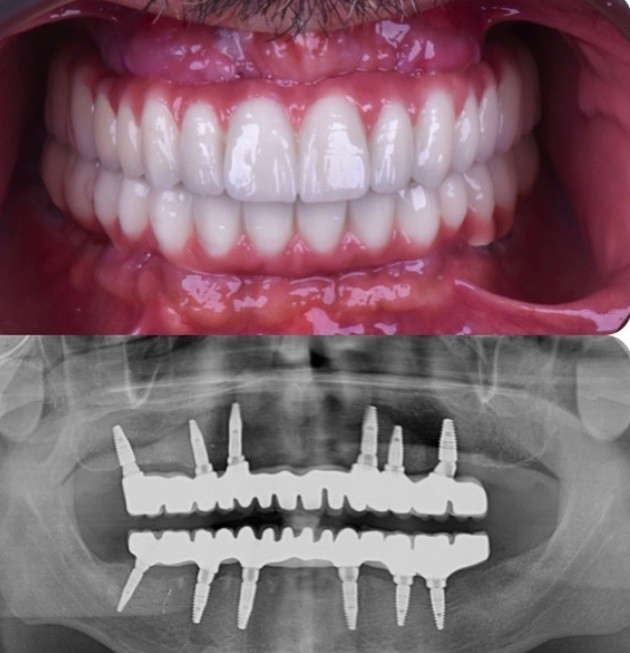

ایمپلنت یک جراحی دهانی است که در آن ابتدا، یک ایمپلنت از جنس تیتانیوم در استخوان فک قرار داده می شود و پس از بهبودی استخوان و لثه، اتصال دهنده و تاج دندان بر روی آن نصب میشود و ظاهری طبیعی و کاملا شبیه به دندان دارد.

ایمپلنت های دندانی نوعی کاشت دندان در دندانپزشکی ترمیمی و زیبایی است که برای جایگزینی دندان های از دست رفته مورد استفاده قرار می گیرد. کاشت دارای 2 قسمت است:

لنگر فلزی

دندان کاذب، شبیه به تاج.

کاشت دندان مانند دندان طبیعی به نظر می رسد و احساس طبیعی بودن را القا می کند.

لنگر فلزی وارد استخوان فک می شود.

پس از قرار دادن لنگر، یک دندان کاذب در جای خود قرار می گیرد.

این موارد در مورد جایگزینی دندان های از دست رفته بسیار پرطرفدار هستند. این روش در دندانپزشکی ترمیمی و زیبایی مستلزم ترکیب شدن پست های تیتانیوم به فک با یک دندان مصنوعی پیچ شده در بالای آن است. ایمپلنت نزدیکترین چیز به دندان های طبیعی در نظر گرفته می شود زیرا پست های تیتانیوم به عنوان ریشه دندان عمل می کنند و رشد استخوان را تحریک می کنند، در حالی که پروتزهای دندانی و پل های دندانی چنین نیستند.

ایمپلنت دندان امروزه استانداردترین روش مراقبت از جای خالی دندان از دست رفته و استخوان فک در حال تحلیل است.

در روش ایمپلنت نیاز به تراشیدن دندانهای سالم مجاور نیست، ظاهر دندان ایمپلنت بسیار مشابه دندان طبیعی بوده و با دندان طبیعی تفاوت ظاهری ندارد و هیچگونه فشار اضافهای روی لثه ندارد.